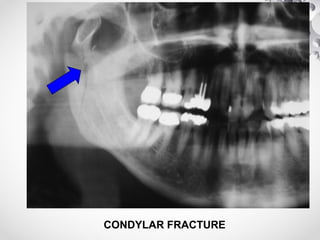

CONDYLAR FRACTURE

CLINICAL FEATURES

• # of Condyle

(1) Tenderness over TM joint

(2) Trismus

(3) Jaw deviation to injured side, on mouth opening

(4) Dental malocclusion